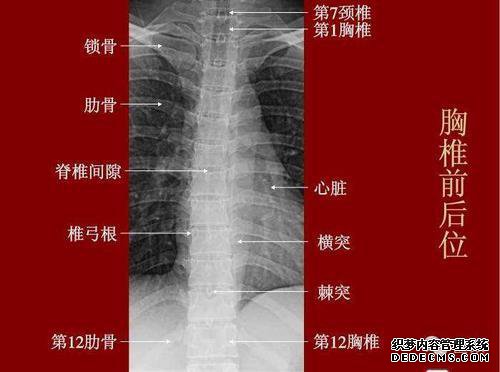

地图集和尾椎解剖图。